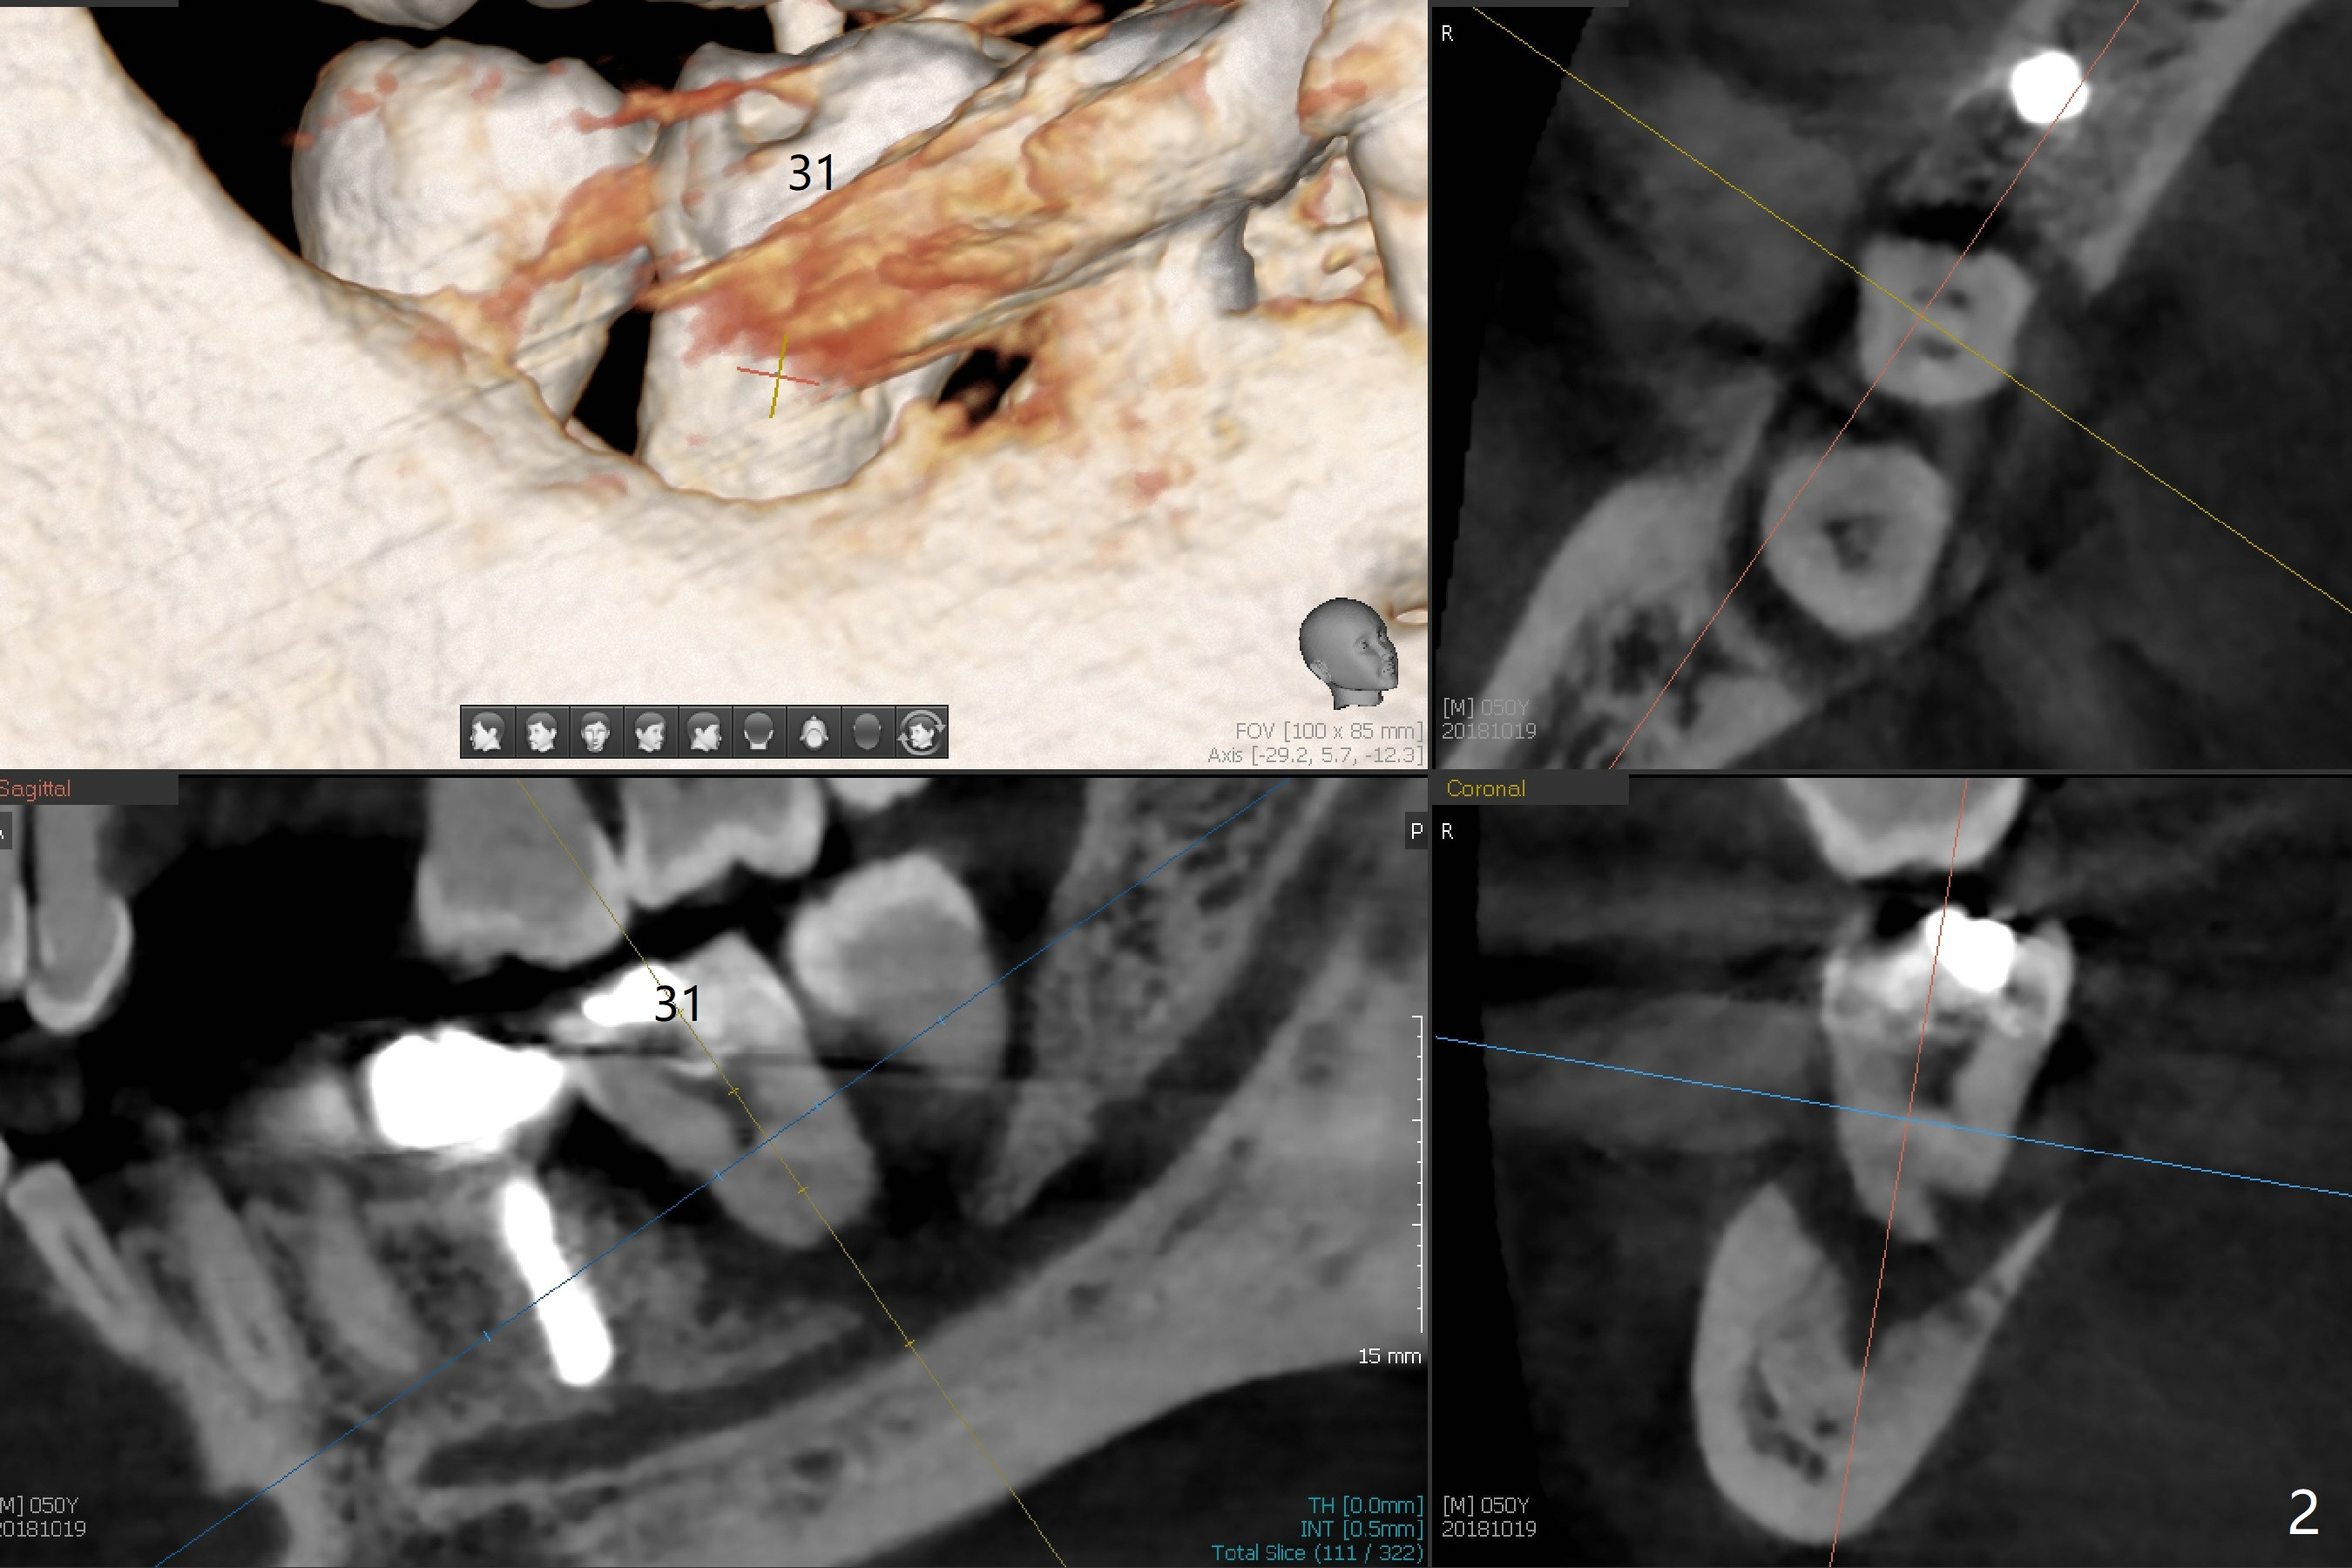

A 50-year-old man with severe chronic periodontitis and bruxism returns to clinic with chief complaint of a loose bottom right back tooth at #31 after implant placement at #19 and 30 (Fig.1,2). How to treat this case?